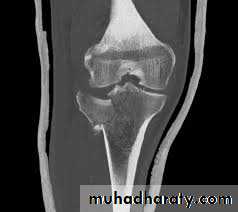

Tibial plateau fractures:Direct blow or fall from height may cause fracture of one tibial condyle or both.

Fracture lateral condyle is the commonest named as bumper fracture

caused by a force that abducts the tibia upon femur while the foot is fixed on ground.Patient usually is an adult, the knee joint is swollen, bruises, there is diffuse tenderness and doughy feel of haemarthrosis.

ligaments injuries must be excluded.

Imaging : X-ray

: anteroposterior, lateral & oblique views.

CT -Scan may used to detect amount of depression and comminuation.Tibial plateau fracture

Treatment:

Undisplaced fractures

treated conservatively:Haemarthrosis aspiration and compression bandaging,

above knee cast for one monthsfollowed by functional brace and physiotherapy.

For displaced fracturestreatment is by open reduction and internal fixation with

plate and screws as it is an intra articular fracture.fixation of tibial plateau fracture